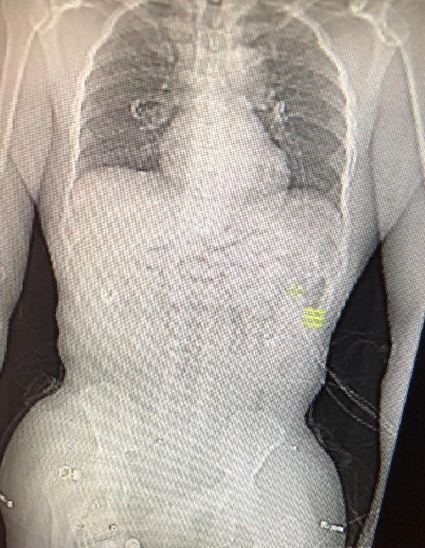

Uyuşturucu kuryeliği yaptığı şüphesiyle gözaltına alınan şahsın hastanede çekilen röntgen kontrollerinde midesinde 93 kapsül metamfetamin diye tabir edilen uyuşturucu madde olduğu tespit edildi. Gözaltına alınan şahıs emniyetteki işlemlerinin ardından adliyeye sevk edildi. (İHA)İlginizi Çekebilir

Foto: İHA